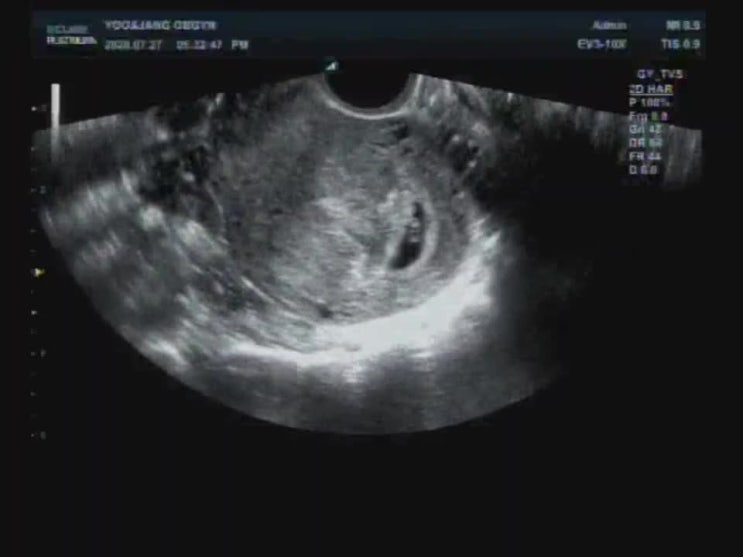

[(산후)둘째임신기록] (1) 임신확인...산부인과 전원

사소한 기억은 가물가물하지만 출산의 기억은 뚜렷하다!! 일단 남겨보자.. 2020년 7월초, 임신 사실을 알게...